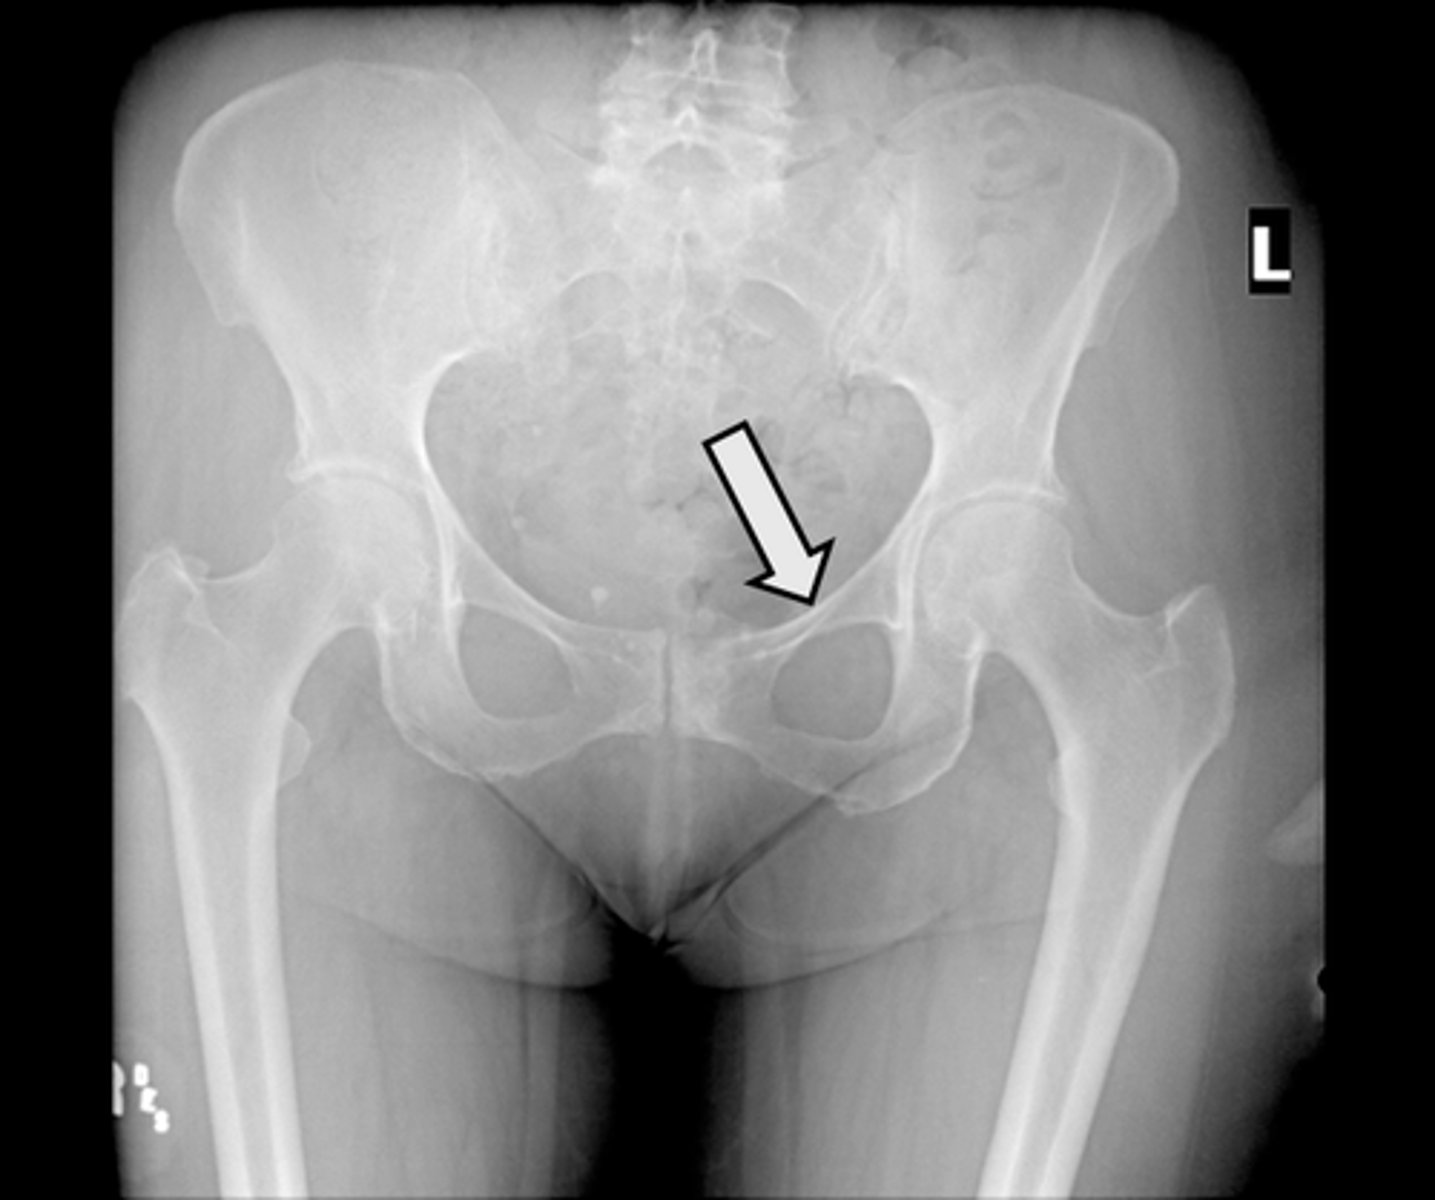

Looks like no tags are added yet.

AP pelvis

What is the image?

<p>What is the image?</p>

L acetabulum

<p>What is indicated in the image?</p>

L anterior superior iliac spine (ASIS)

L ilium

L ischial tuberosity

L obturator foramen

L sacroiliac joint

L superior ramus of pubis

R acetabulum

R anterior superior iliac spine (ASIS)

R ilium

R ischial tuberosity

R obturator foramen

R sacroiliac joint

R superior ramus of pubis

Sacrum